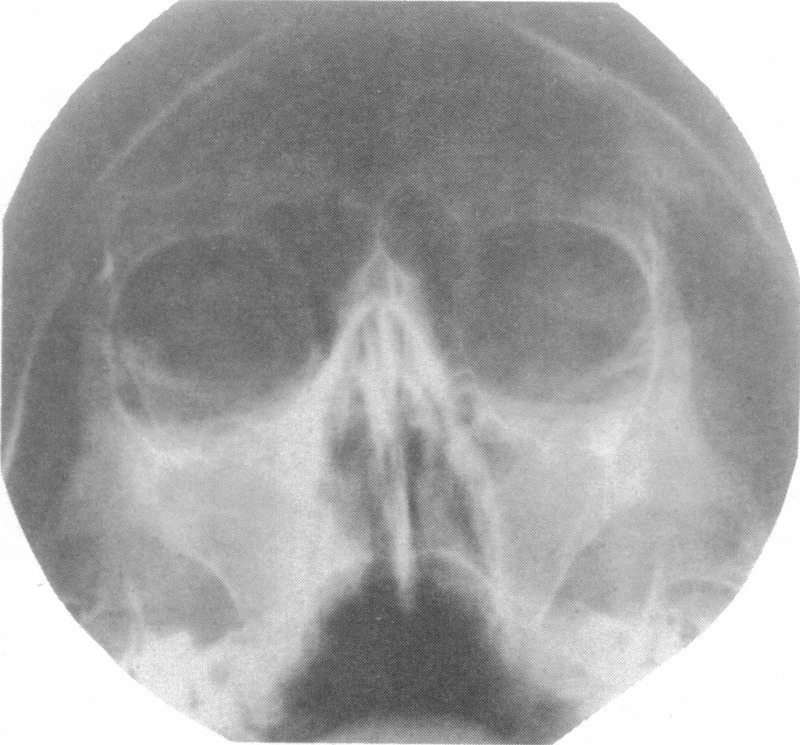

limits. An EKG showed nonspecific ST-segment and T wave abnormalities. A CT scan performed

with contrast is shown in panel B below.

Panel B. Computerized tomographic scan performed with contrast demonstrating bilateral mediastinal adenopathy.

The main clues to the diagnosis in the presented case is the finding of bilateral

hilar and paratracheal adenopathy in conjunction with anterior uveitis. The diagnosis

was confirmed by performing a biopsy of the mediastinum which showed extensive replacement

of lymph node tissue by confluent noncaseating acid fast and culture negative granuloma.